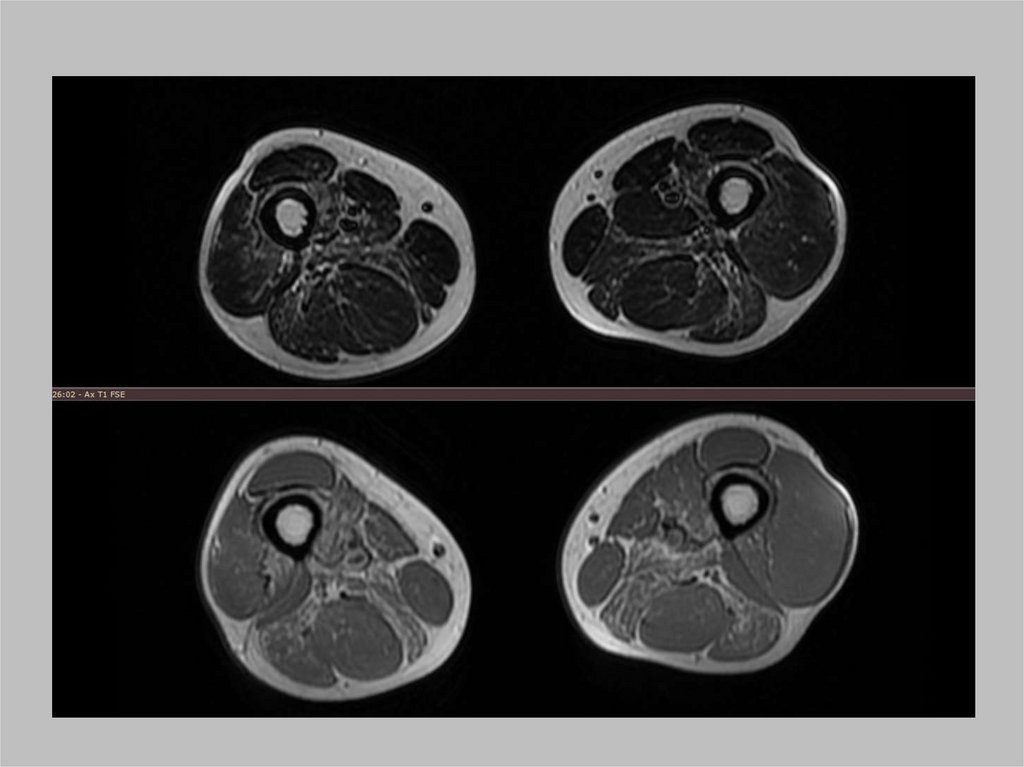

Перелом шейки бедра

22.

Эндопротез тазобедренного сустава

23.

24.